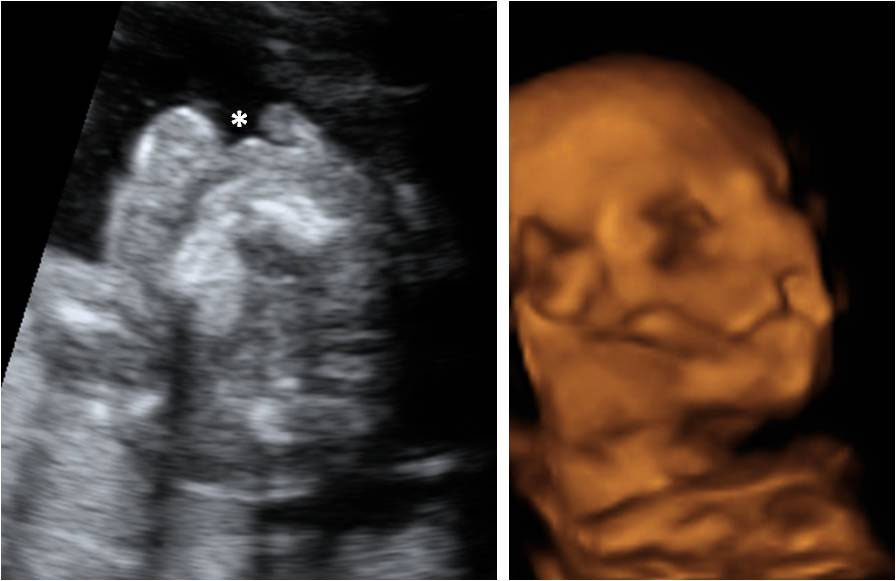

En esta imagen obtenida con una ecografía en 4D de un feto de 20 semanas de gestación se contempla cómo el bebé mueve sus brazos delante de su cara. Aún se encuentra muy delgado, ya que es a partir del tercer trimestre, sobre todo, cuando el feto empieza a acumular grasa bajo su piel.

Ecografía de bebé de 20 semanas de perfil

Podemos ver claramente los miembros superiores: el feto flexiona los brazos y los pasa por delante de la cara